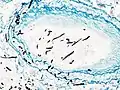

| Tomosynthesis of chronic fibrosing pulmonary aspergillosis | |

On microscopy, Aspergillus species are reliably demonstrated by silver stains, e.g., Gridley stain or Gomori methenamine-silver.[27] These give the fungal walls a gray-black colour. The hyphae of Aspergillus species range in diameter from 2.5 to 4.5 μm. They have septate hyphae,[28] but these are not always apparent, and in such cases they may be mistaken for Zygomycota.[27] Aspergillus hyphae tend to have dichotomous branching that is progressive and primarily at acute angles of around 45°.[27]